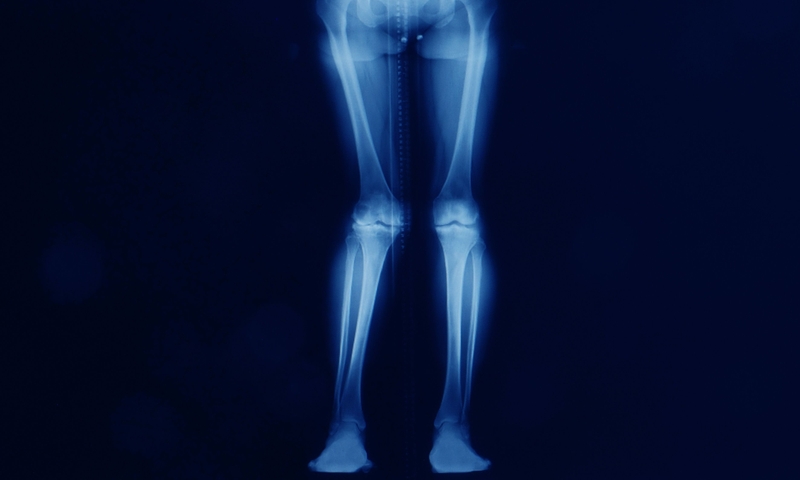

Bệnh xương hóa đá là một bệnh khiến xương quá đặc và sự bất thường này dẫn đến xương dễ gãy. Bệnh khiến các huỷ cốt bào (tế bào huỷ xương) hoạt động bất thường. Bình thường, các huỷ cốt bào sẽ phá vỡ mô xương đã cũ khi có mô xương mới phát triển.

Bệnh xương hóa đá còn được gọi là bệnh Albers-Schonberg hoặc Osteopetrosis là một bệnh liên quan đến rối loạn di truyền cực kỳ hiếm gặp khiến xương cứng và trở nên đặc hơn. Rối loạn này có thể gây xơ cứng xương (osteosclerosis). Nó biểu hiện dưới hai dạng lâm sàng chính, dạng gen trội trên nhiễm sắc thể thường (lành tính) và dạng gen lặn trên nhiễm sắc thể thường (ác tính).

Bệnh xương hóa đá được đặc trưng bởi tình trạng cấu trúc xương quá dày đặc. Các triệu chứng bao gồm gãy xương, thiếu máu và mất chức năng thần kinh sọ gây mù, điếc và/hoặc liệt dây thần kinh mặt. Ngoài ra người bệnh có thể bị nhiễm trùng thường xuyên ở răng và xương hàm.

Người bệnh có xương cứng bất thường (xơ cứng xương); xương dễ gãy, thường là xương sườn và xương dài; đầu to và hàm nhỏ; chậm phát triển và tăng mật độ xương sọ dẫn đến chèn ép các dây thần kinh. Người bệnh cũng có thể bị não úng thủy, gây tăng áp lực lên mô não.